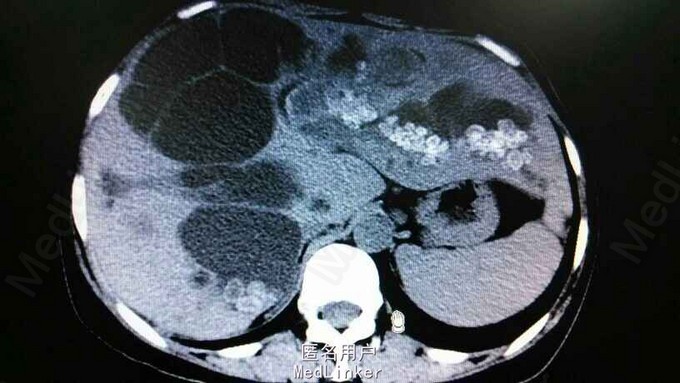

查体:右上腹轻压痛,无反跳痛,余无特殊。辅助检查,肝功,血象正常。腹部CT示肝内多发结石伴胆管囊状扩张。胆总管结石。见图